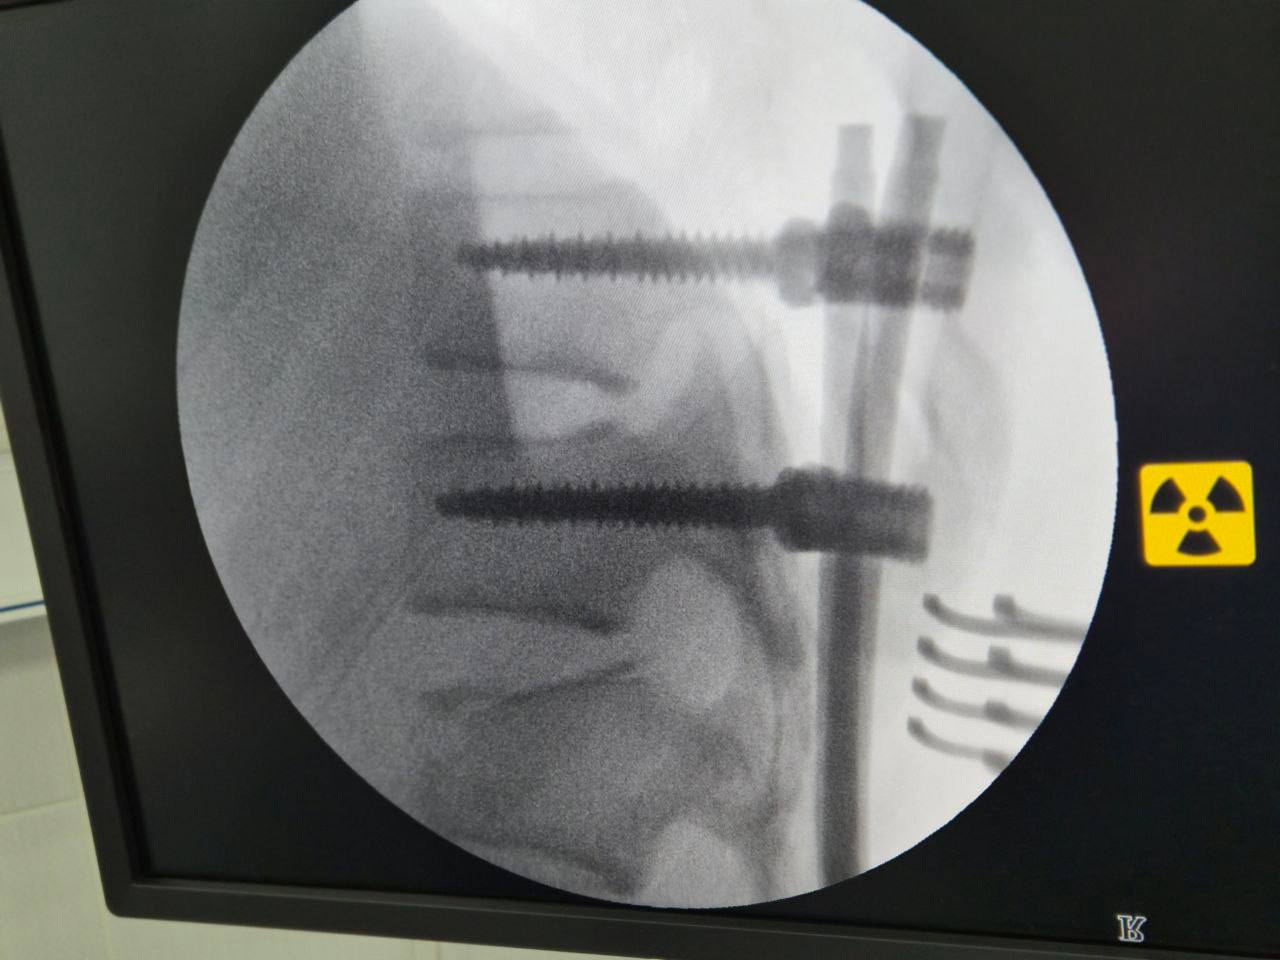

Медики успішно виконали складне нейрохірургічне втручання — транспедикулярну стабілізацію хребта. Такі поранення є надзвичайно небезпечними, оскільки нестабільність хребта може призвести до ураження спинного мозку та незворотних наслідків.

Під час високоточної операції нейрохірурги встановили транспедикулярні гвинти та фіксуючу систему, що дозволило стабілізувати ушкоджений сегмент хребта, відновити його анатомічне положення та створити умови для подальшого зрощення й реабілітації.